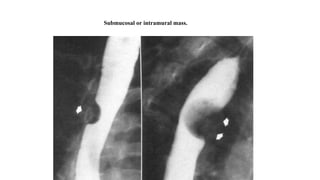

Submucosal or intramural mass.